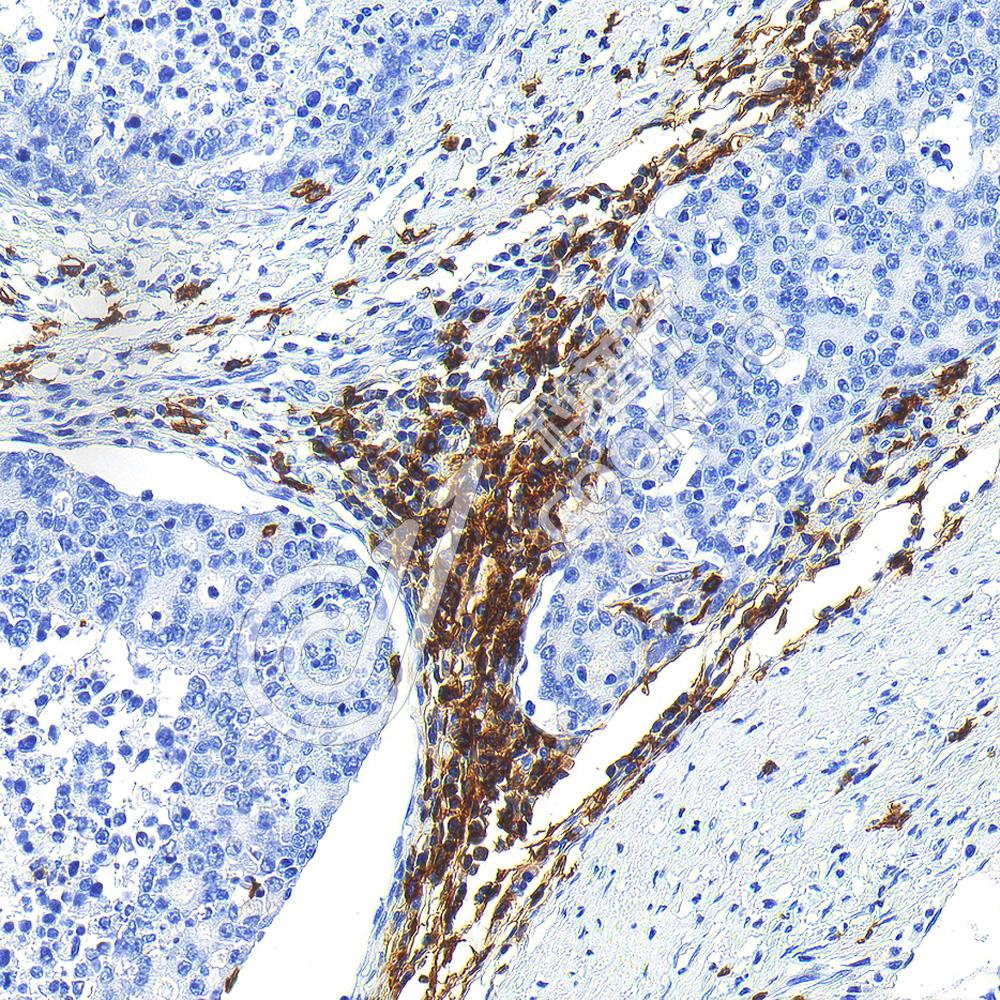

IHC检测CD19蛋白(货号 K133183-1).

样品: 人淋巴瘤, 4%多聚甲醛 (货号KSG1101) 固定12-24小时.

抗原修复: 柠檬酸抗原修复液(干粉, pH 6.0) (KSG1201), 98℃, 20分钟.

—抗: 1: 600稀释, 4℃ 孵育过夜.

二抗: S-vision免疫组化多聚二抗(山羊抗兔),即用型 (货号KB3906), 室温孵育20分钟.